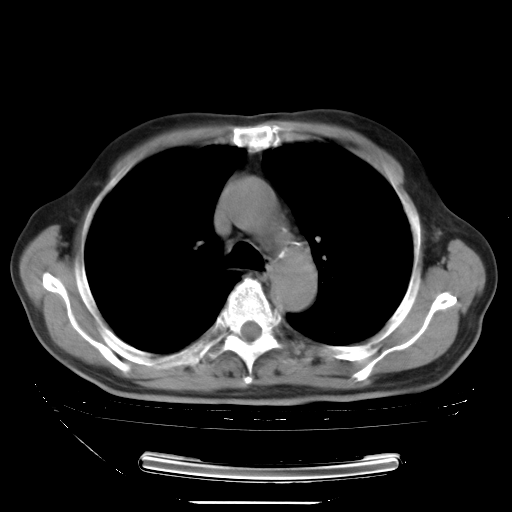

今天复查肺部CT,发现双肺广泛磨玻璃样改变。所以我把3月19日和5月9日相隔50天的肺部CT上传。请大家会诊。

5月9日肺部CT(在4月27日齐鲁医院肺部CT描述部分肺组织磨玻璃样改变,12天后肺组织广泛磨玻璃样改变)

大致读了系列胸部CT:纵隔窗无明显异常,肺窗:从4、27至今:主要是双肺中下野外带可见毛玻璃样改变,目前处于急性肺泡炎阶段,至于原因考虑1、结替组织或胶原血管性疾病所致?2、恶性疾病如恶组在肺部所致的表现或细支气管肺泡癌?3、药物或其它原因如肺蛋白沉着症所致肺泡炎目前不太可能?总之,明天就去请我院的呼吸科、感染科、血液科和临免专家会诊哈。